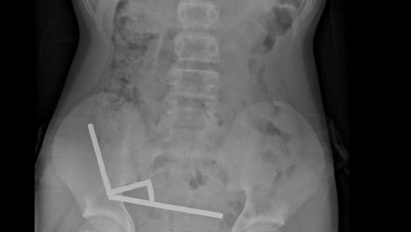

Adolescente perde parte do intestino após engolir mais de 80 imãs